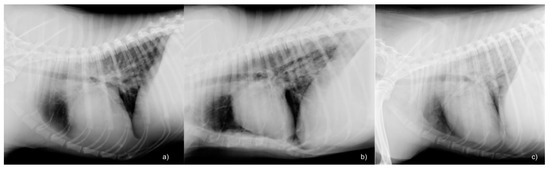

| Radiological abnormalities | 6/10 (60%) | 17/37 (46%) | 0.177 Phi: 0.211 | |

| Radiological pattern Alveolar pattern Interstial-alveolar pattern Unstructured interstitial | 2/6 (33%) 3/6 (50%) 1/6 (17%) | 3/17 (18%) 5/17 (29%) 9/17 (53%) | 0.225 Phi: 0.325 | |

| Radiological pattern distribution Cranial Caudal Diffuse | 1/6 (17%) 1/6 (17%) 4/6 (66%) | 1/17 (6%) 11/17 (65%) 5/17 (29%) | 0.193 Phi: 0.340 | |